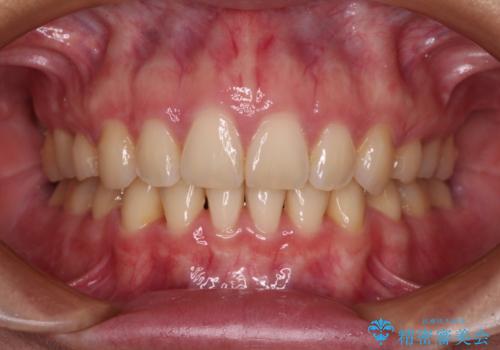

奥歯1歯分を動かすには時間がかかるため、矯正治療には思いの外時間がかかりました。

痛みのある奥歯は必要に応じて根管治療を行い、左下インプラントは角化歯肉の移植により清掃性を向上させ、気になっていた部分をしっかりと改善させることができました。